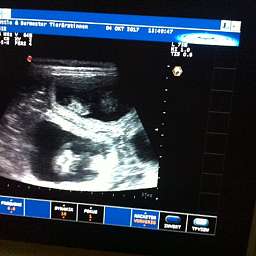

4.10.2017, 35.Tag: Der Ultraschall brachte 5 kleine Wunder zutage. Gesund und munter mit Herzschlag und Bewegung. Elise meisterte alles mit Bravour. Mit Ruhe, Vertrauen und Engelsgeduld ließ sie alles über sich ergehen. Ich bin sehr stolz auf unsere Kleine. Es sind also mindestens 5 Welpen unterwegs. Schaut doch mal: